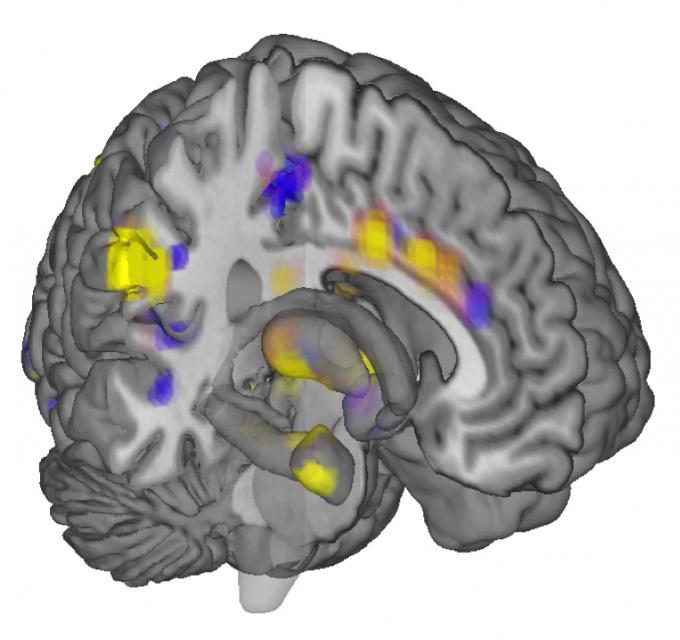

Cercetătorii americani au analizat cu ajutorul unui computer imaginile creierelor a 114 persoane, realizate cu un dispozitiv de scanare atunci când voluntarii erau expuşi în faţa unor intensităţi diferite dureroase, cauzate de aplicarea unor stimuli termici pe piele.

Cu ajutorul unui program computerizat, oamenii de ştiinţă au putut să identifice astfel semnătura neurologică a durerii.

„Am descoperit reacţii similare în multe zone ale creierului care corespund intensităţii durerii resimţite de acele persoane care răspuns la căldura aplicată”, explică Tor Wager.

Şi, contrar aşteptărilor, aceste semnături cerebrale ale durerii nu erau specifice fiecăruia dintre participanţii la acest studiu, ci erau similare între ele.

Astfel, cercetătorii au putut să prezică cu un grad de acurateţe de 90% până la 100% nivelul durerii pe care o persoană o resimte, atunci când aceasta era confruntată cu intensităţi diferite ale unor stimuli termici aplicaţi pe piele.